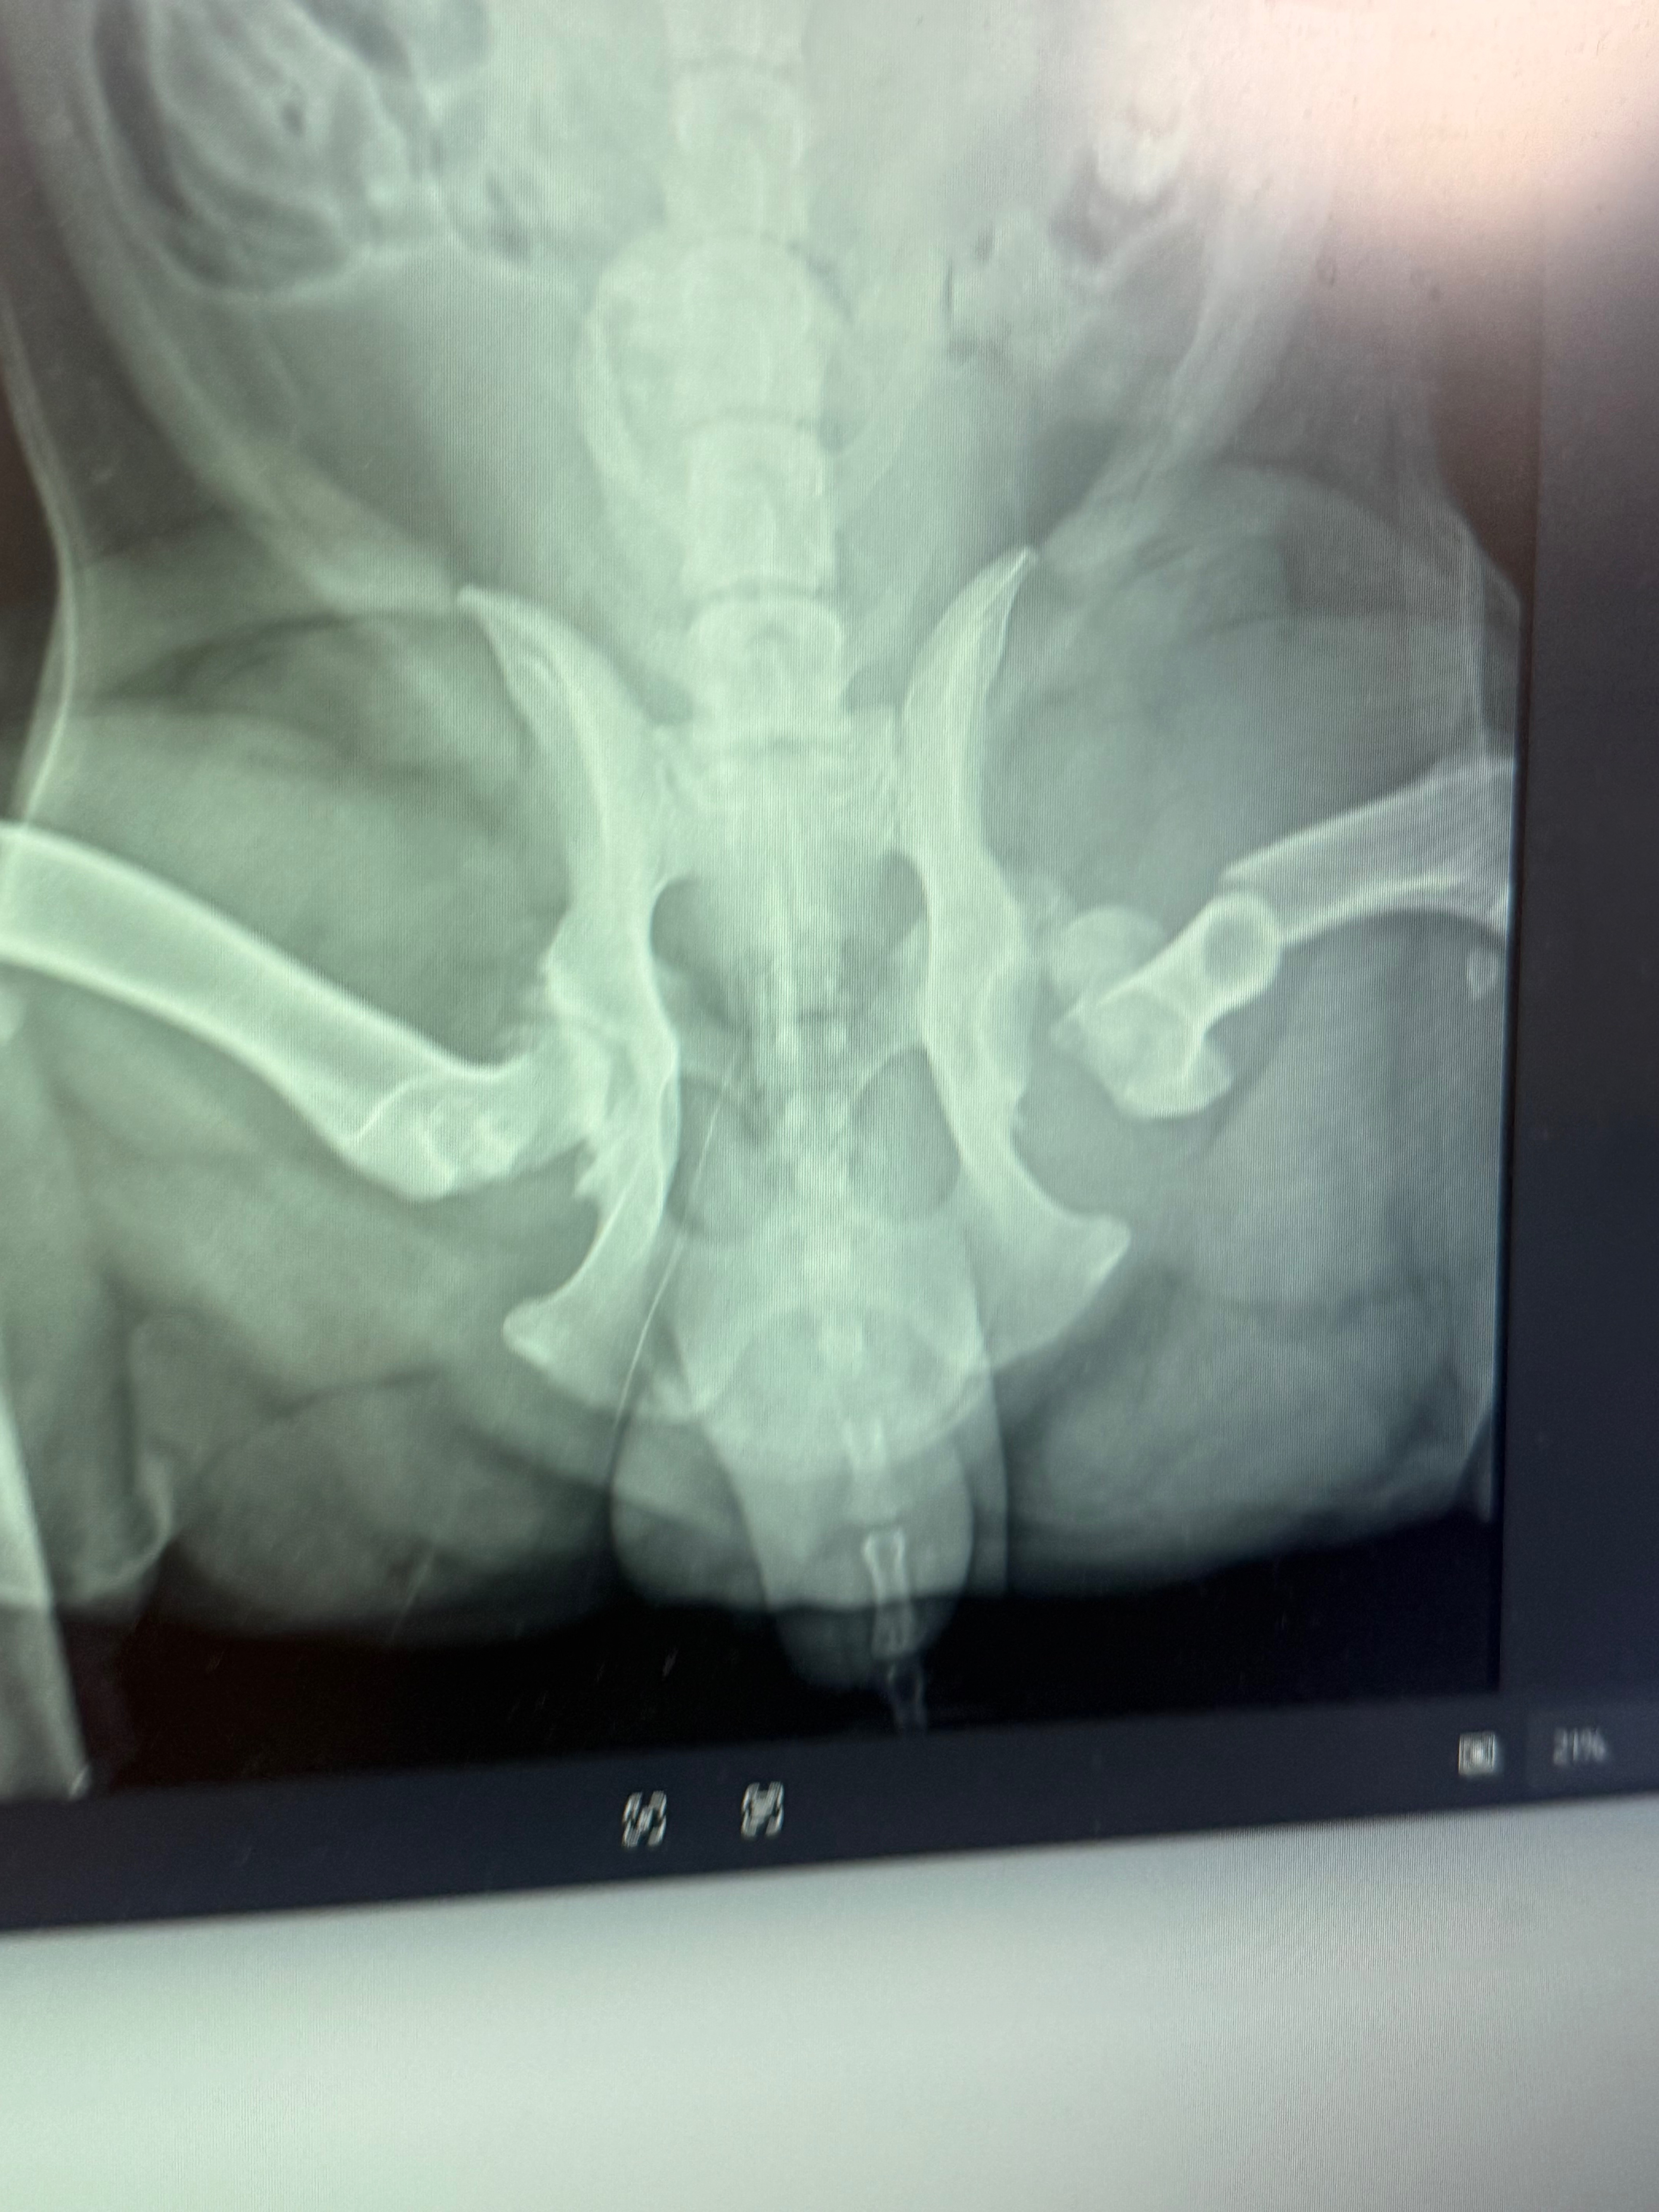

Koda suffered a broken leg, bruised lungs and heart, and several other serious injuries. He is currently on constant oxygen and receiving intensive veterinary care as doctors work tirelessly to stabilize him and give him the best chance at recovery. The road ahead will include surgery, continued hospitalization, medications, and rehabilitation.

• Surgery and follow-up care for the broken leg